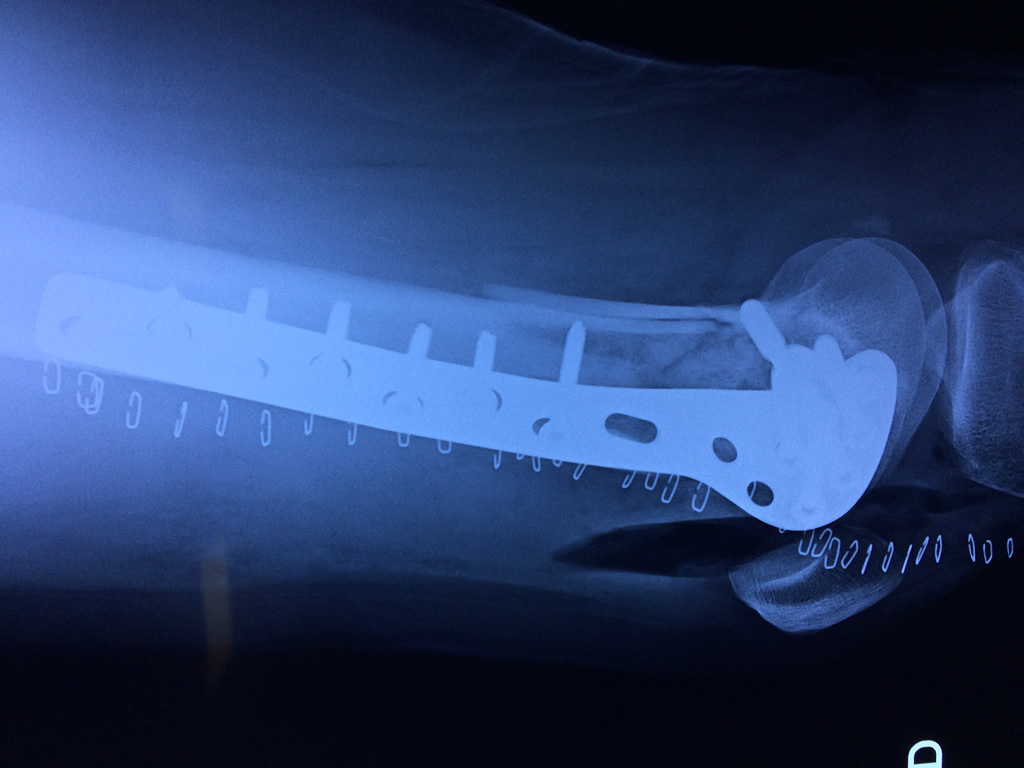

Cirugía de Rodillas

El fémur es el hueso del muslo, el segundo segmento del miembro inferior. Es el hueso más largo, fuerte y voluminoso del cuerpo humano.